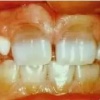

Puudub ülemine tsentraalne intsisiiv